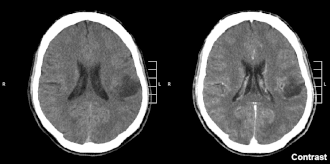

Glioma no lobo parietal de segundo grau em CT scan cerebral.